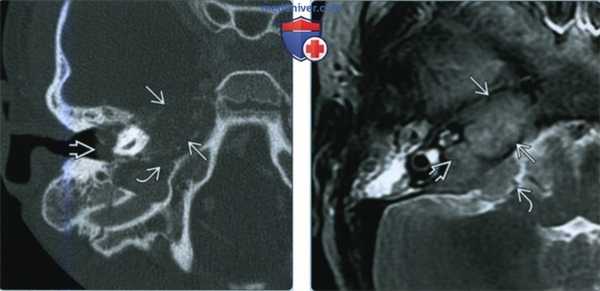

(Слева) При аксиальной МРТ Т1 ВИ у пациента с онемением правой половины лица определяется типичный метастаз в вершине пирамиды, замещающий жировой костный мозг, с распространением в полость Меккеля справа. Обратите внимание на нормальный сигнал в коаном мозге вершины пирамиды слева и ЦСЖ в полости Меккеля.

(Справа) При КТ определяется метааатическое поражение сосцевидного отростка с деструкцией кортикального слоя с внутренней аороны/сигмовидной пластинки с риском инвазии/тромбоза сигмовидного синуса. Из-за особенностей строения/пневматизации височной кости маленькие метастазы легко пропускаются.